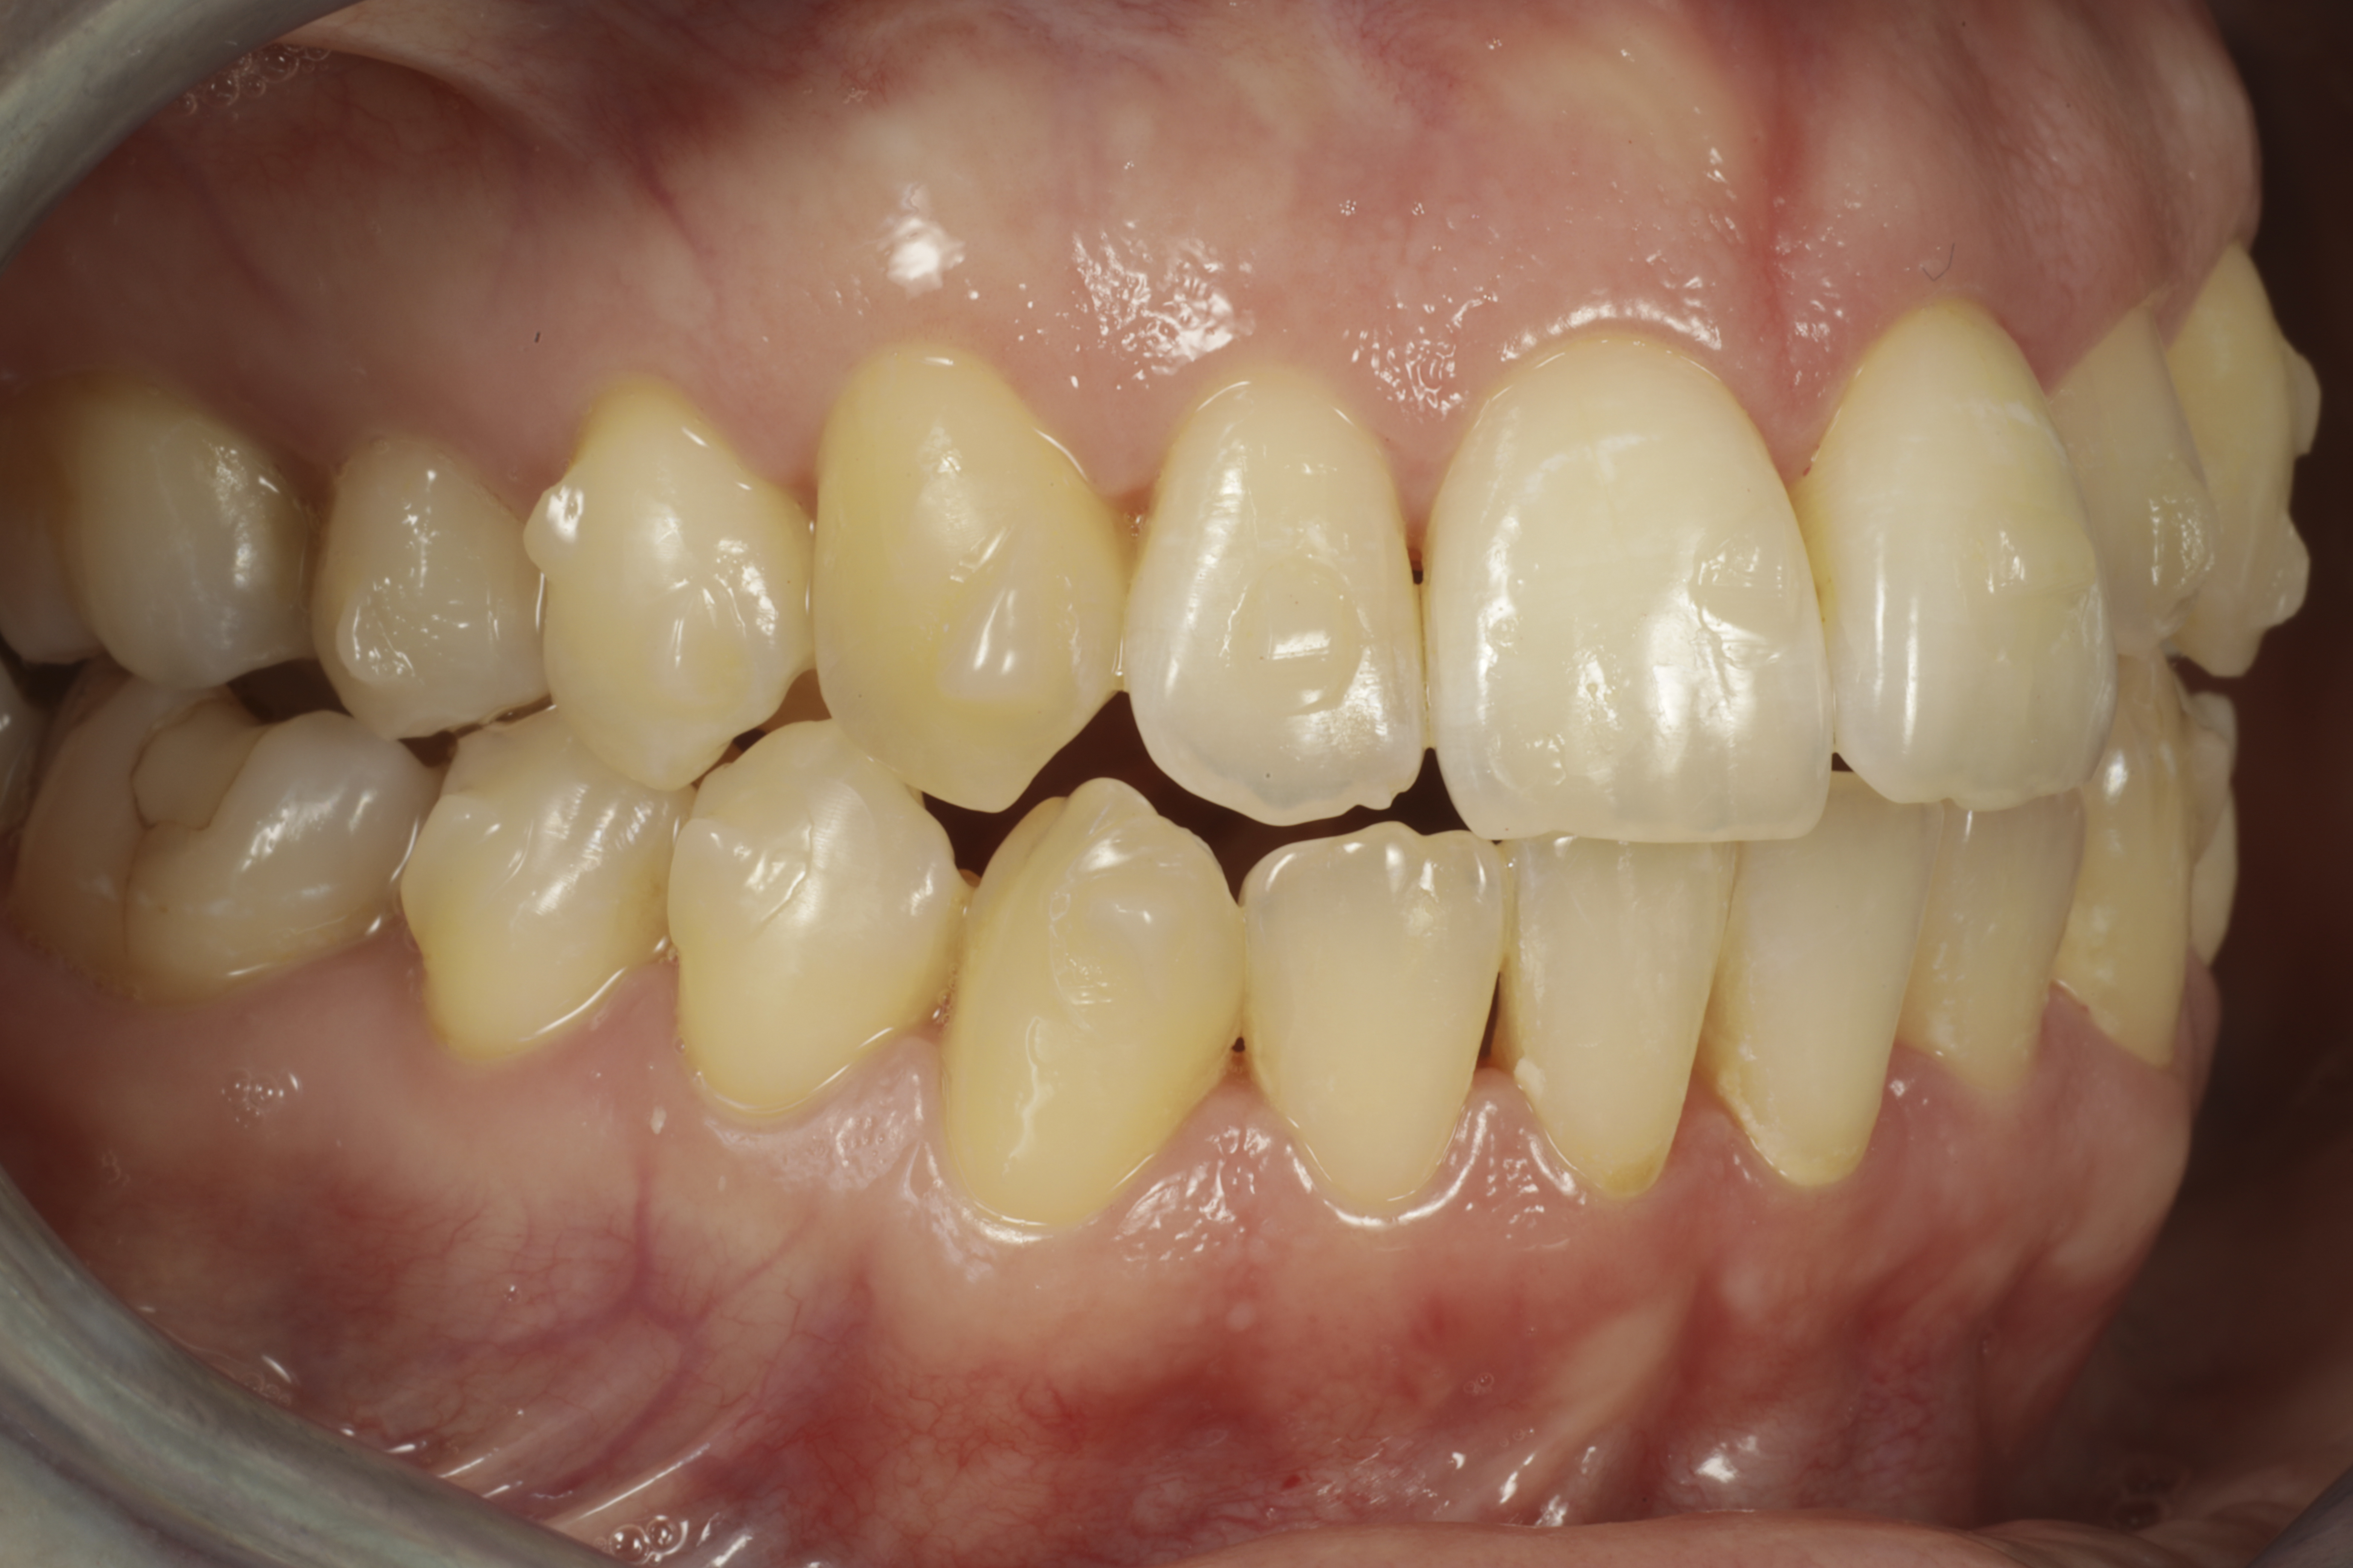

Alla suorittamiani hoitoja ja esimerkkejä siitä minkälaisia purentavirheitä voi korjata.

10kk hoito (Comprehensive). Etuhampaiden kärkien viimeistely kerrostusmuoveilla.